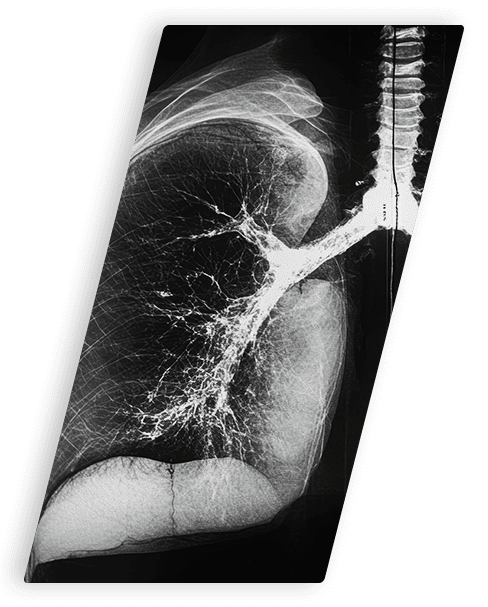

- Pleural – Lungs, Most Common Type

It generally isn’t difficult for doctors to discern one type of mesothelioma from another. This is because the cancer grows directly into body structures near where it formed before spreading to other parts of the body. Doctors will clearly see more tumor growth in the chest cavity with pleural mesothelioma, and more tumor growth in the abdominal cavity with peritoneal mesothelioma.

While the same imaging scans and biopsy techniques are used to diagnose all types of mesothelioma, the name and location of the procedure will differ depending upon which type of mesothelioma is suspected. Certain minor surgical procedures that help with mesothelioma diagnosis also vary depending upon the suspected mesothelioma type.